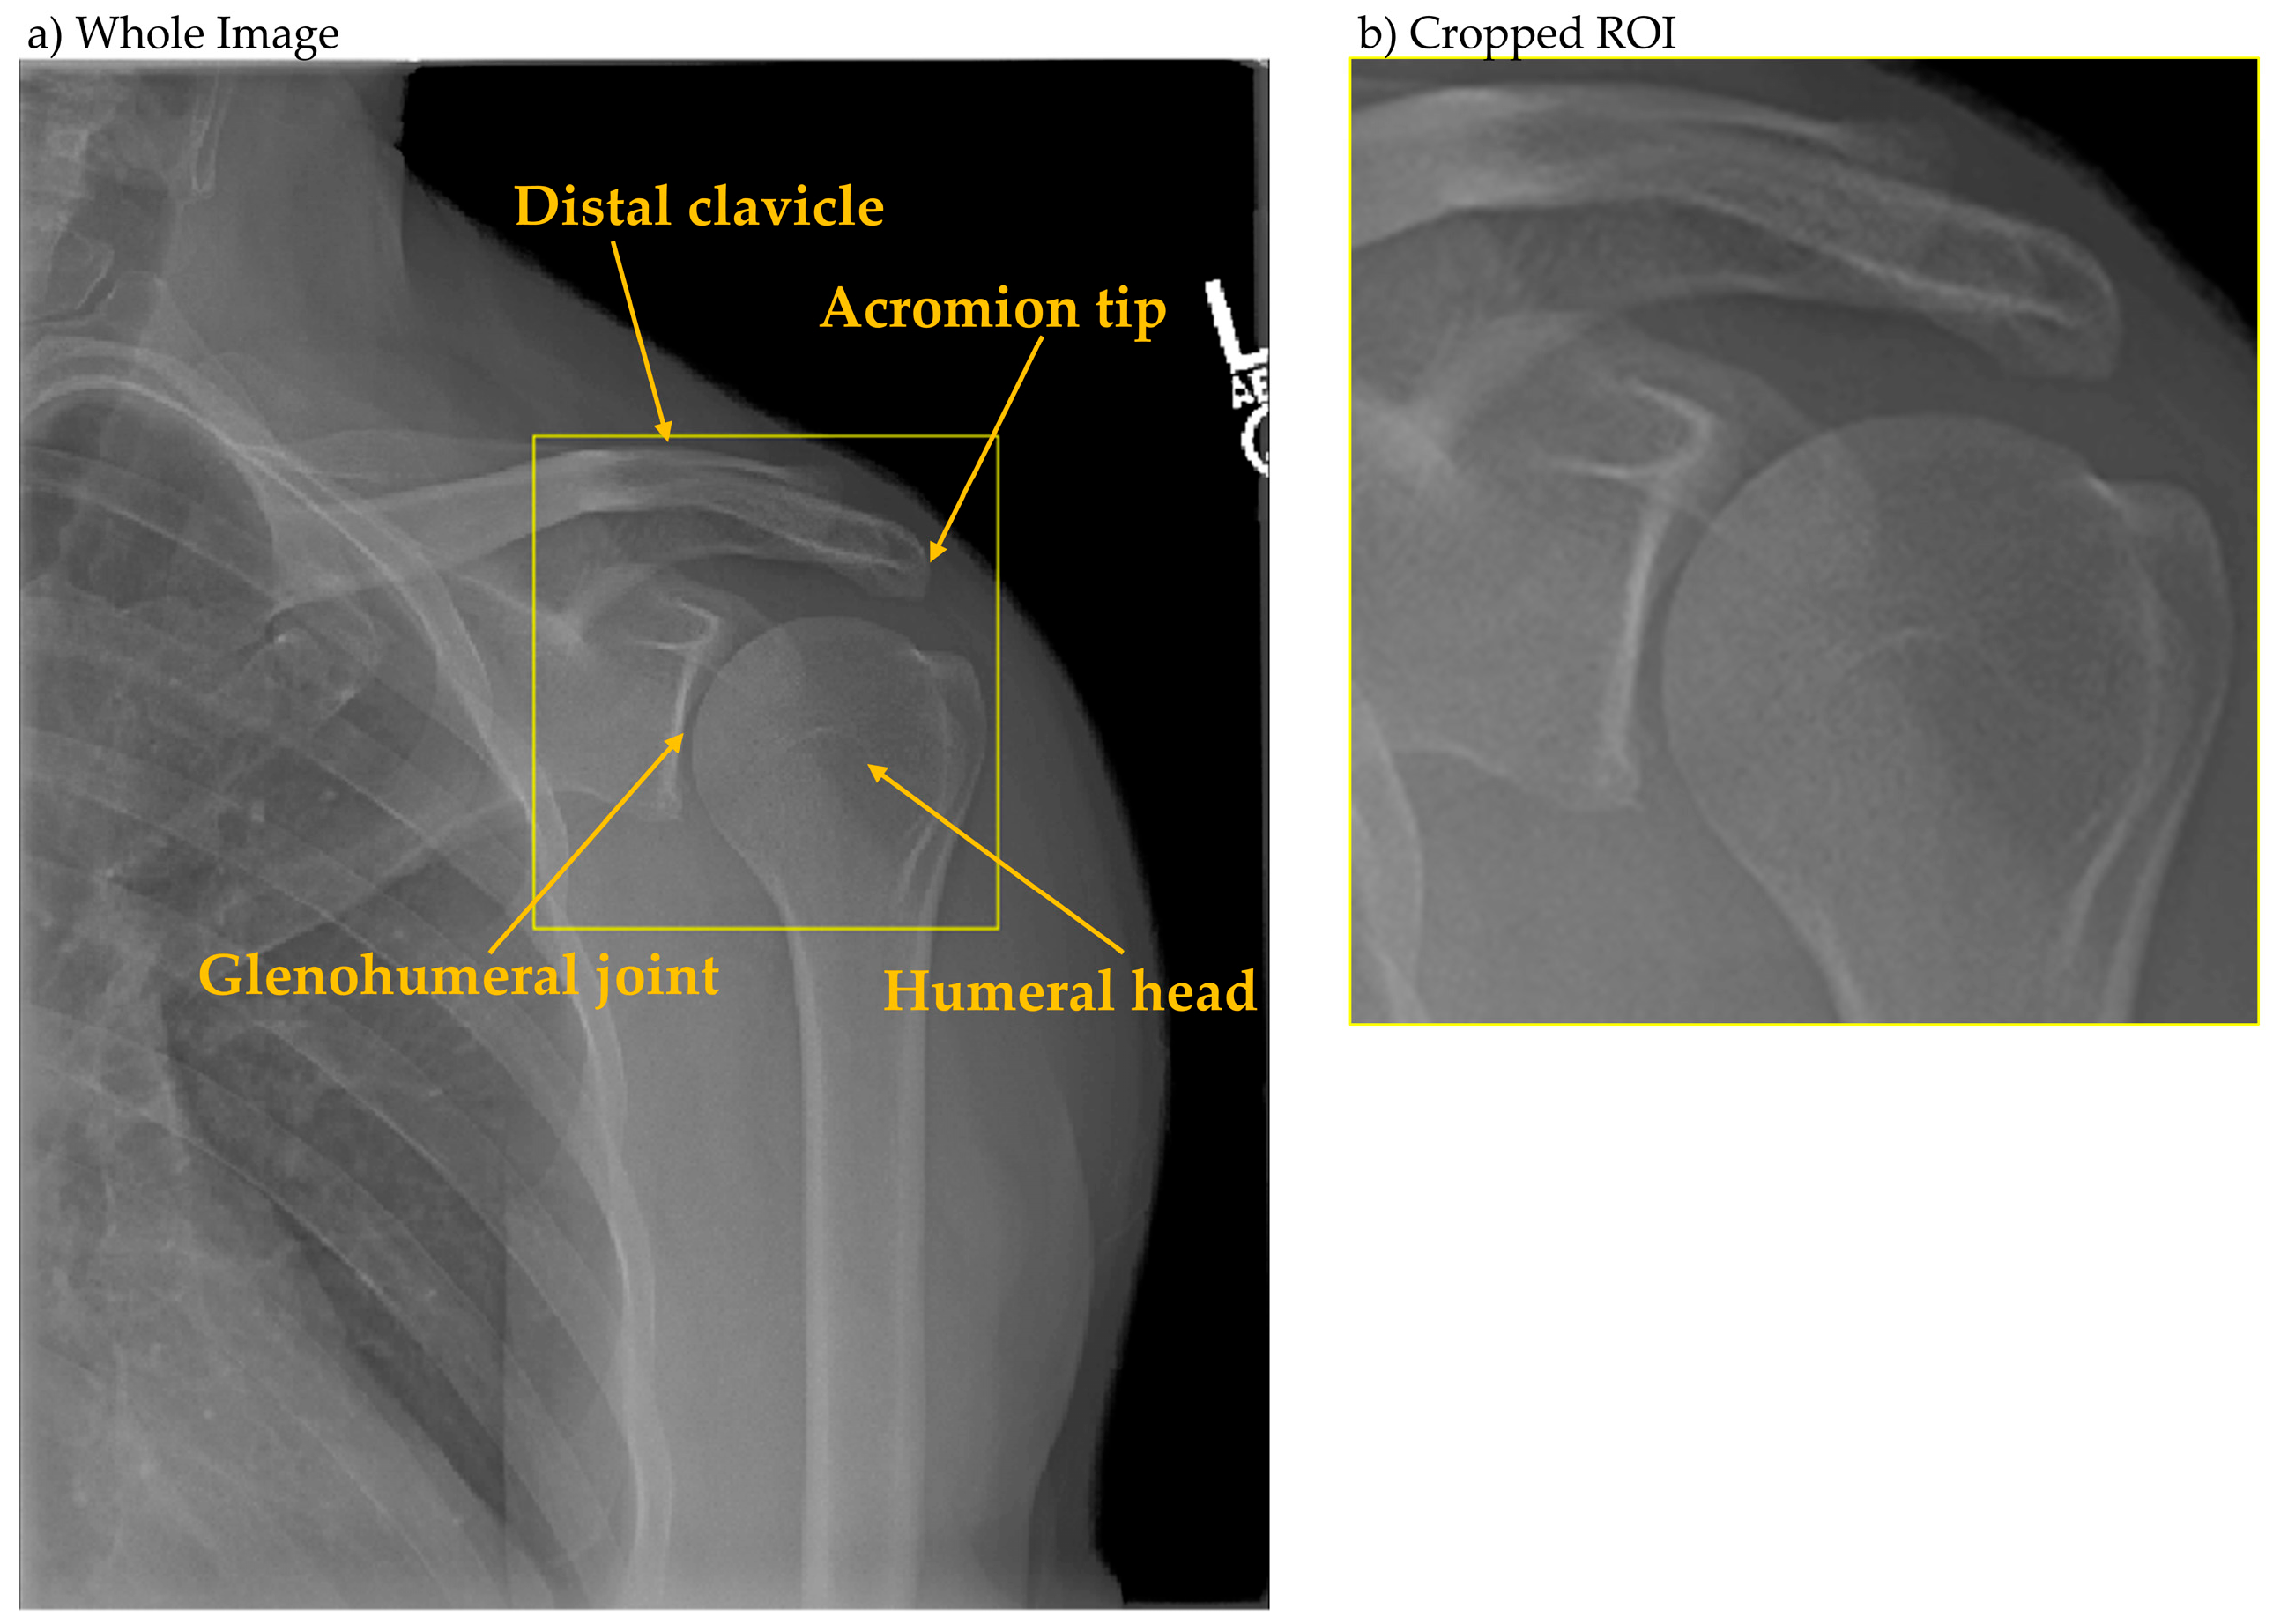

The analytical framework employed a two-stage deep learning pipeline. Stage one utilized YOLOX [19] for glenohumeral joint detection, with the region of interest defined as encompassing the acromion tip, humeral head, and glenohumeral joint space (Figure 2). Ground truth bounding boxes were established through consensus annotation by three radiographers. Stage two employed Inception-ResNet-v2 [20] for binary quality classification (OK/NG), processing both whole images and locally cropped regions extracted using stage-one detection boxes, both of which were resized to 299 × 299 pixels to match the input resolution of Inception-ResNet-v2. The overall workflow of our two-stage pipeline is illustrated in Figure 3. Explainability was implemented via Grad-CAM for both classifiers; maps were overlaid and summarized using coverage metrics as detailed in Section 3.3.

Figure 2. Definition of glenohumeral joint detection region. (a) Whole shoulder anteroposterior radiograph. (b) Cropped image of the yellow region of interest in (a).